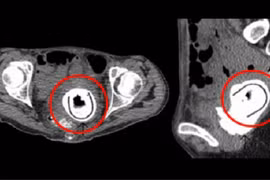

(khoahocdoisong.vn) - Nhiều trường hợp bệnh nhân nam sử dụng các dụng cụ hỗ trợ tình dục để tự sướng đường hậu môn, một số dị vật trôi vào trong trực tràng.